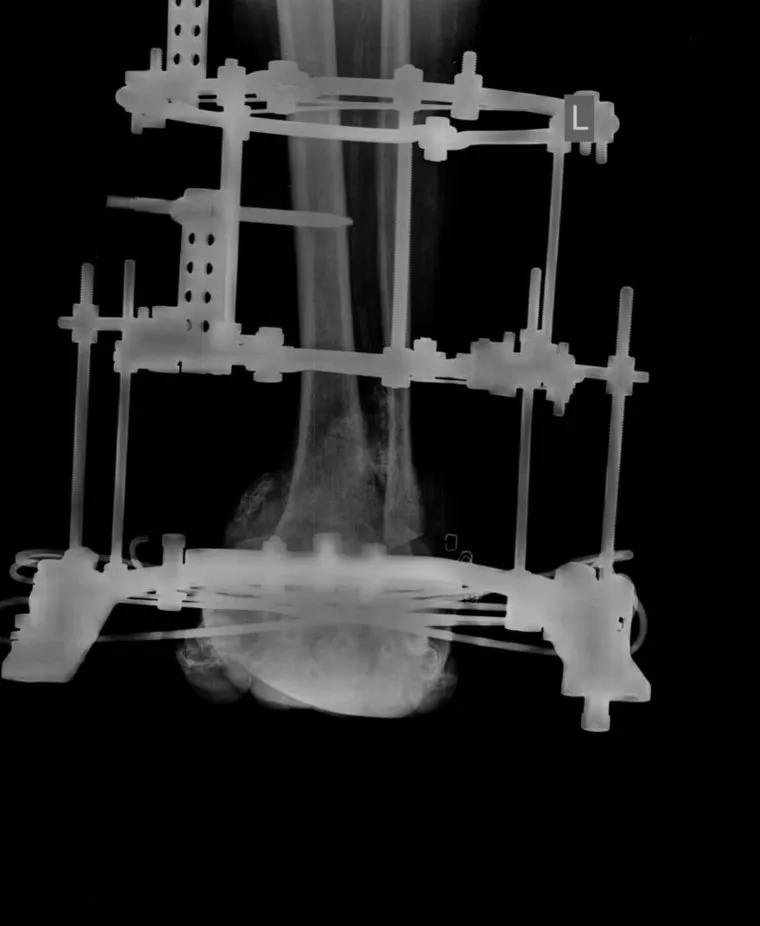

В Центре Илизарова в Кургане врачи спасли стопу 64-летнего пациента из Омана, страдающего диабетической стопой Шарко. В других клиниках мужчине предлагали ампутацию. Благодаря использованию усовершенствованного аппарата Илизарова и методу чрескостного остеосинтеза удалось сохранить ногу, рассказали в пресс-службе медицинского учреждения.

«64-летний пациент из Омана приехал в Курган с надеждой сохранить конечность. На фоне сахарного диабета у него развилось ортопедическое осложнение — нейроостеоартропатия, больше известное как диабетическая стопа Шарко. Его мучила обширная незаживающая рана на левой стопе. В Центре Илизарова жителя Омана госпитализировали в гнойное травматолого-ортопедическое отделение №2. Операцию провел заведующий научной лабораторией Клиники костно-суставной инфекции Анатолий Судницын», — сообщили в Центре.

Благодаря методу Илизарова пациенты с диабетической стопой становятся мобильными уже на вторые сутки после операции. Стабильность аппарата и ранняя нагрузка создают условия для нормализации кровоснабжения и заживления ран. Центр Илизарова ежегодно принимает более 200 пациентов из-за рубежа, предлагая высокотехнологичные методы лечения и возвращая людей к полноценной жизни.

В иностранных клиниках мужчине предлагали ампутацию больной стопы, тогда он обратился в Центр Илизарова, пользуясь ресурсами телемедицины

Курганские врачи проконсультировали пациента дистанционно, а через некоторое время он приехал из Омана в Курган на операцию